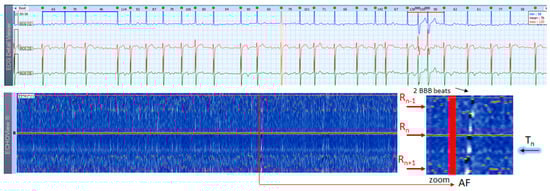

AF is the most common arrhythmia among humans (1 of 4 will have at least 1 episode of this arrhythmia in his/her life). This rhythm disorder and the less common AFL are usually not difficult to be recognized in standard 12-lead ECG strips if the ventricular rate is not too high and the fibrillation ‘f’ waves or flutter ‘F’ waves are visible in at least one lead. However, if HR is very high and irregularity of the rhythm, and fibrillations (in AF) or ‘saw-like’ fluctuations of the isoelectric line (in AFL) are not visible, it could be difficult to say what kind of arrhythmia the patient has. In addition, in many patients these arrhythmias are transitory and sought by Holter ECG/event recorders, which records frequently have a lot of artifacts due to physical activities and other factors. In such cases, ECHOView may help to recognize AF/AFL arrhythmias because they have a very characteristic pattern on the color map, as shown in Figure 13, Figure 14 and Figure 15. The notable behavior of AF is the absence of a P-wave band and scattered dots of R-wave peaks (Figure 13 and Figure 14), while AFL has presence of several F-wave bands and stable band of R-wave peaks (Figure 15). Beneficially, these ECHOView maps sufficiently differ from the patterns of other high-rate arrhythmia, such as SINT (Figure 6, Figure 7 and Figure 8), SVA (Figure 9) and PSVT (Figure 10, Figure 11 and Figure 12).

ECHOView interpretation turned out to be very important for some of our patients with episodes of supraventricular rhythm disorders such as SINT, SVT, AF and AFL. These arrhythmias are very common among the general population, affecting both younger and older people, with or without underlying cardiac injury [1,2,3,4,5,6,7]. A lot of non-cardiac conditions such as thyroid dysfunction, chronic lung diseases, electrolyte disturbances, infections (including COVID-19), etc. could also ‘unlock’ SVAs [1,2,8]. The diagnosis is based mostly on non-invasive ECG methods, mainly standard 12-lead ECG and 24–72 h Holter ECG monitoring [1,2,3,4,5,6,7,8,9,10]. Standard 12-lead ECG records are obtained in rest and their quality is usually much better than Holter ECG records, but conventional ECGs are not the ideal tool for diagnosing arrhythmias. They present time frames of about 10–20 s and many patients with SVAs could be missed because arrhythmias are often transitory [1,2,3,4,5,8]. For this reason, diagnosis is usually obtained by Holter ECG monitoring or event recorders [1,2,3]. However, most of these devices record less number of channels (1 to 3) in which P-waves of the normal sinus rhythm may not be demonstrated [1,2,3,4,5,6]. In addition, external factors such as movements, posture, skin contact of the electrodes, etc. may exert significant influence on the quality of the records and the morphology of ECG components, thus making the detection of P-waves even more difficult [1,8,17]. One of the most common ECG challenges is the differentiation of a high-rate sinus tachycardia from other SVTs (AVNRT, AVRT, focal AT) and sometimes from high-rate AF/AFL. Physical activities, emotions, panic attacks, pain/severe discomfort, febrility, etc. may cause expressed sinus tachycardia with complaints indistinguishable from a true tachyarrhythmia [3,5,9]. The ECG leads to shortening of the RR intervals, the impossibility of recognizing regularity/irregularity of the rhythm, and identifying/distinguishing the normal sinus P-wave from pathological P-waves of AT, F waves of AFL and f-waves of AF could make diagnosis uncertain, particularly if the patient has already had arrhythmias or risk factors for the development of them [5,7,9]. In this article we present several cases in which patient’s complaints and the Holter ECG records required differentiation between SINT, SVT and AF/AFL. In our cases, ECHOView facilitated the accurate diagnosis clearly disclosing the P-wave in SINT (Figure 6, Figure 7 and Figure 8) and the pathological atrial excitations in cases of true tachyarrhythmias SVT (Figure 10, Figure 11, Figure 12 and Figure 16), AF (Figure 13, Figure 14 and Figure 16) and AFL (Figure 15 and Figure 16) but also the contrastive ventricular pattern of NSVT. As the prognostic significance and therapeutic approach to arrhythmias can vary greatly [40], such as the need for oral anticoagulation in AF/AFL [1,2], the advanced perspective of ECHOView is an important tool to improve risk assessment and therapeutic decision-making.

4.3. ECHOView: Summary of the Principles of Imaging

The color-coded ECG amplitudes of sequential beats produce an intuitive trace of different intervals (PnRn, RnTn, Rn−1Rn, RnRn+1, etc.) in a visible image (width × height = 1740 beats × 1500 ms) within one ECHOView page. Without a specific measurement, this visual effect resembles the rendering of one-dimensional time trends of automatically measured ECG intervals. These trends show stable PnRn and RnTn intervals during the NSR part of the examples in Figure 4, Figure 5, Figure 6, Figure 7, Figure 8, Figure 9, Figure 10, Figure 11 and Figure 12. The trends are also informative for the RR-intervals (Rn−1Rn, RnRn+1) on a beat-by-beat basis that is helpful for identifying long-term HR changes in high-rate SINT (Figure 6, Figure 7 and Figure 8) and AFL (Figure 15), as well as rhythm, transitions NSR→ paroxysmal SVA (Figure 9), NSR→PSVT (Figure 10, Figure 11 and Figure 12), NSR→NSVT (Figure 10, Figure 11 and Figure 12), and AF→AFL→ST (Figure 16).